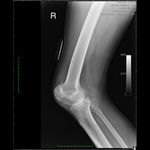

Patient seen with Bilateral Knee Pain and had been unable to walk for two (2) years.

On clinical and radiological examination, he was assessed as having Severe Primary Osteoarthritis of both knees.

Bilateral Total Knee Replacement was recommended, and performed on July 27th 2011. Since surgery, the patient has made good progress and can now mobilize with the aid of a walker.

His x-rays and clinical examination suggest good early outcome with a fully mobilized patient with pain free knees and the ability to walk independently.